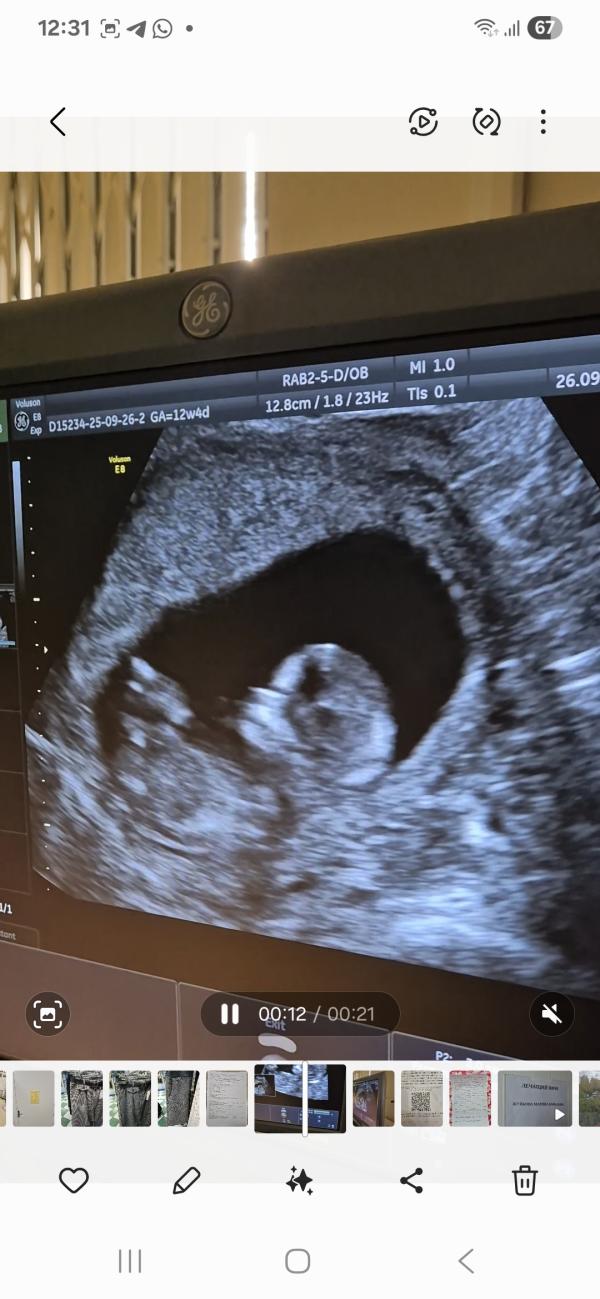

Наконец можно выдохнуть и полноценно наслаждаться беременностью. Первый скрининг пройден, результаты на генетические заболевания сегодня получили. С малышом всё отлично, никаких рисков. Расти наш малыш, мы так тебя ждём! Это просто непередаваемые ощущения, за 2 года планирования, после замершей на 8 неделе, и моей раздавленности и теряющейся с каждым месяцем надежды, у нас всё хорошо. Кто с таким столкнулся, тот поймёт. Так интересно всё же жизнь складывается, я бы никогда не подумала что я захочу не 1 ребёнка, а несколько, в 28 лет я готова была кричать чаечкой, что многдетные родители не в себе и голову надо лечить, как же я ошибалась. За это время я побывала в разных статусах беременной: сначала малолетняя первородящая, мне полных 17 было, затем обычная, теперь старший репродуктивный возраст. Предстоит ещё консультация у генетика, (об этом сразу предупредили), кто был что там происходит?